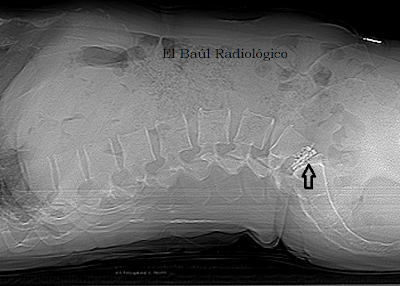

En los últimos años del siglo pasado los avances experimentados en la especialidad de Diagnóstico por Imagen han sido espectaculares. Por eso, a veces, se nos escapa una sonrisa socarrona cuando alguno de los colegas no sabe distinguir entre una imagen de Tomografía Computarizada y otra de Tomografía por Resonancia Magnética. Pero.....¡cuidado¡, hay que ser prudentes porque las innovaciones tecnológicas se han producido en todos los campos de la Medicina y tambien nosotros nos podemos llevar alguna sorpresa. ¿Qué es eso? ¿Qué lleva ahí? ¿Se ha quitado todo lo que llevaba en el pantalón? son algunas de las preguntas que nos hacemos cuando comienzan a aparecer las imágenes de una exploración de TRM en la pantalla de la consola de adquisición de datos y vemos algún objeto que no sabemos identificar.

Los dispositivos más raros y variados que se suelen encontrar en cualquier imagen radiográfica, son los que utilizan los traumatólogos y neurocirujanos para estabilizar las vértebras de la columna lumbar. Como son de titanio no suelen contraindicar ninguna exploración de TRM. Tampoco se calientan, ni se mueven. En cambio, en los exámenes de TC producen numerosos artefactos radiales, como cualquier otro metal.

(The most rare and varied devices that we usually find are those used by orthopedic surgeons and neurosurgeons, to stabilize the vertebrae of the lumbar spine. Here are some very specific models of interspinous metal implants used in our hospital. Made of titanium, they not contraindicate any exploration of MRI. Neither heat, nor moved. In contrast, in CT examinations they produce many radial artifacts, like any other metal)

Protesis+000.png

FIGURA 1) En esta imagen de TRM de la columna lumbosacra se aprecia un objeto extraño (flechas) que no supimos identificar la primera vez que lo vimos. ¿Qué es eso?. ¿Qué lleva ahí? El paciente nos lo aclaró: le habían colocado un implante interespinoso para aliviar el dolor de espalda. ¡aaaaah......¡

(In this image of the lumbosacral spine we can see a foreign object (arrows) that we could not identify the first time we saw it. What is that?. What you got there? The patient said to us: he had got an interspinous implant to relieve back pain).